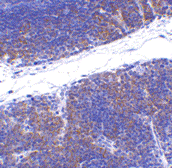

Below: Immunohistochemistry of TNFRSF14 in mouse thymus tissue with TNFRSF14 antibody at 1 µg/ml.